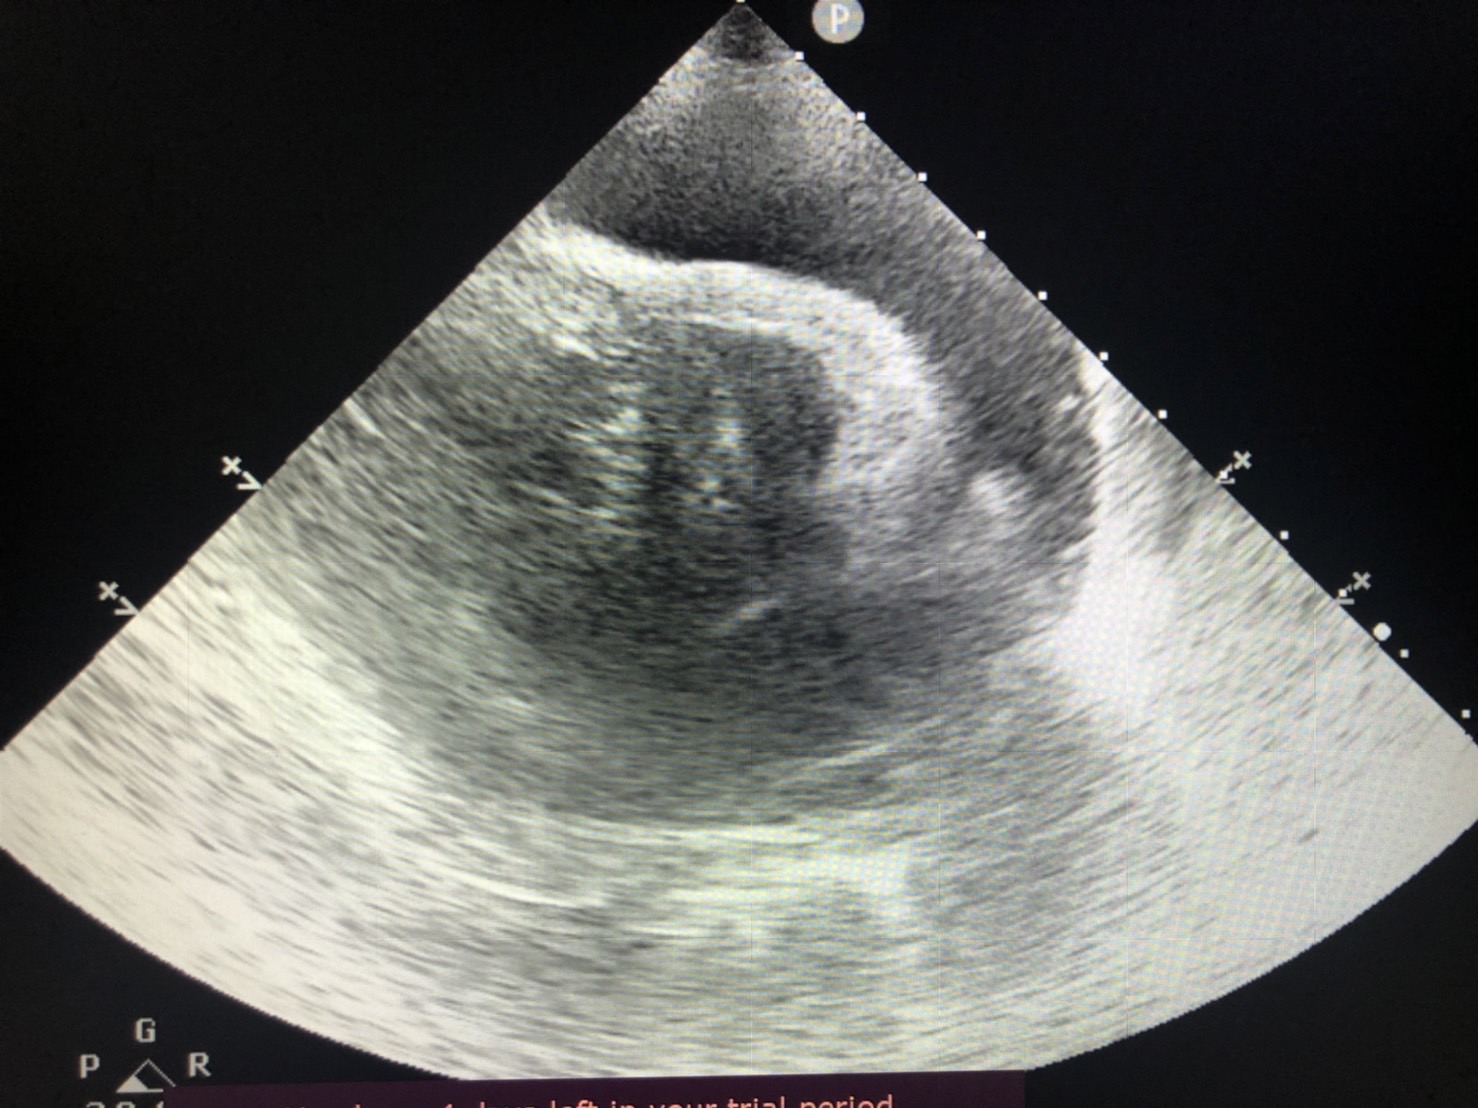

心臟的最外層有一層膜樣構造稱為心包膜,

心臟與膜之間會有少量組織液蓄積其中,達到潤滑的作用。

若是因為腫瘤、心臟疾病、發炎或其他狀況導致液體蓄積在心臟跟心包膜之間,

稱之為心包囊積液。

若是已造成心包填塞的情況下,需抽取心包囊積液,緩解心臟因受到壓迫而造成的致命問題。

同時間需進行身體其他檢查如血液學檢查、X光、心臟超音波等……找到產生心包囊積液的原因。